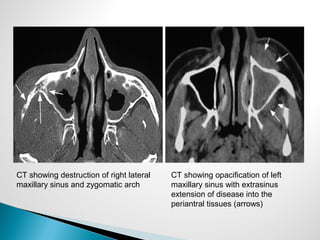

◦ CT & MRI

 Similar findings to AFIFS – bony destruction, extrasinus

extension, unilateral

CT showing destruction of right lateral

maxillary sinus and zygomatic arch

CT showing opacification of left

maxillary sinus with extrasinus

extension of disease into the

periantral tissues (arrows)

 Diagnosis ◦ FullH&N examination with nasal endoscopy  Nasal polyps, thick mucus  Rarely find ulcerations  Biopsy if suspect fungal disease or note any changes ◦ CT & MRI  Similar findings to AFIFS – bony destruction, extrasinus extension, unilateral

• 47.

CT showing destructionof right lateral maxillary sinus and zygomatic arch CT showing opacification of left maxillary sinus with extrasinus extension of disease into the periantral tissues (arrows)